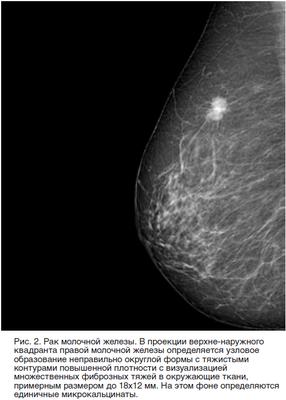

Линейный фиброз молочной

Линейный фиброз молочной 114 фотографий